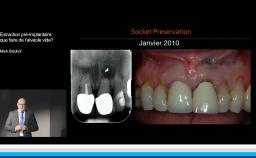

Le moment de l’implantation (immédiate, précoce, différée) influe peu sur le résultat esthétique ; l’implantation immédiate ne supprime pas la résorption physiologique post-extractionnelle.